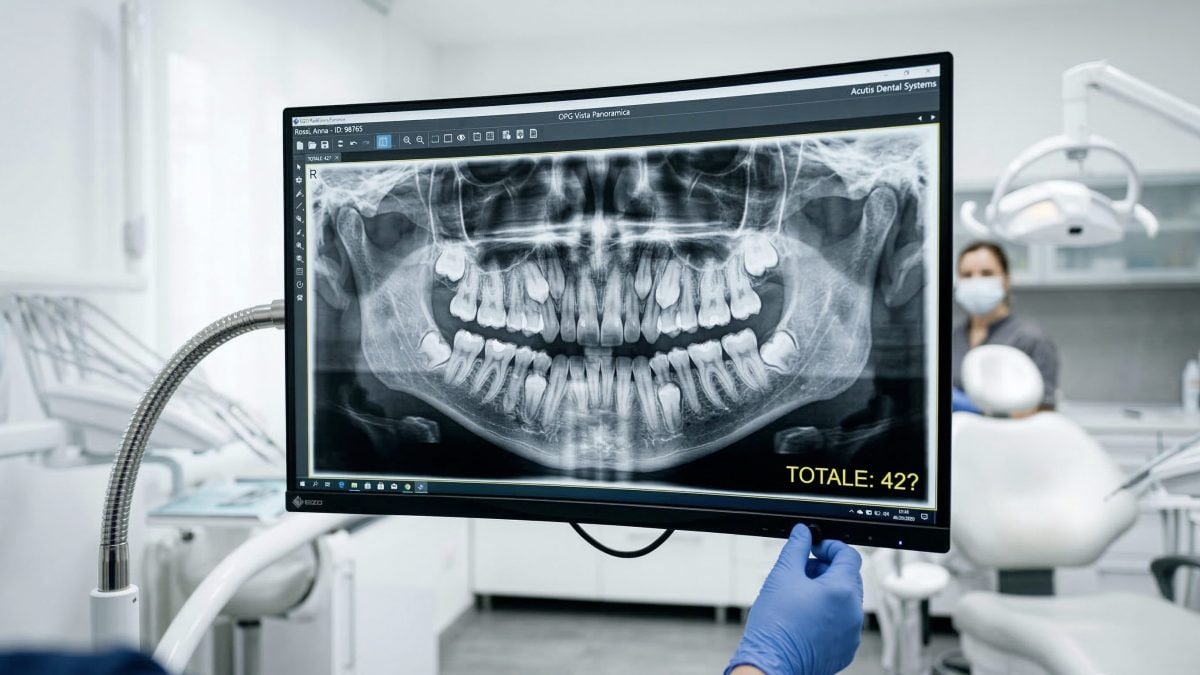

Tra i tanti Guinness World Records legati al corpo umano – dalla donna con i capelli più lunghi fino all'uomo più alto della storia – ce n'è anche uno che riguarda il sorriso: Prathab Muniandy è l‘uomo con più denti al mondo, in totale 42, ossia 10 in più rispetto alla media degli altri esseri umani.

A quel punto, insieme ai suoi parenti avrebbe realizzato di avere in totale 38 denti: la successiva panoramica dentale avrebbe poi confermato la presenza di altri 4 denti pronti a spuntare. La sua storia è stata verificata nel 2023, quando altre due visite dentistiche hanno confermato la presenza di 42 denti totali.

Fortunatamente, i 10 denti in più non hanno causato particolari problemi e, proprio per questo, non gli sono stati rimossi: Muniandy, infatti, detiene il record come uomo con il maggior numero di denti che ancora possiede tutti. Il record femminile, invece, è in mano a Kalpana Balan, una donna indiana che ne possiede 38.